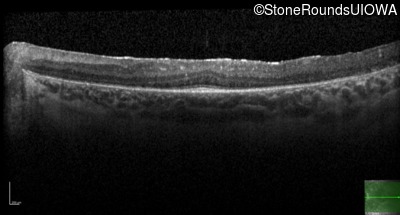

| Age at visit: 27 years |